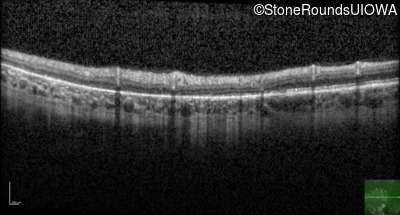

Optical Coherence Tomography - Right - 20/20 -2 sc

Exemplar / OCT Stack